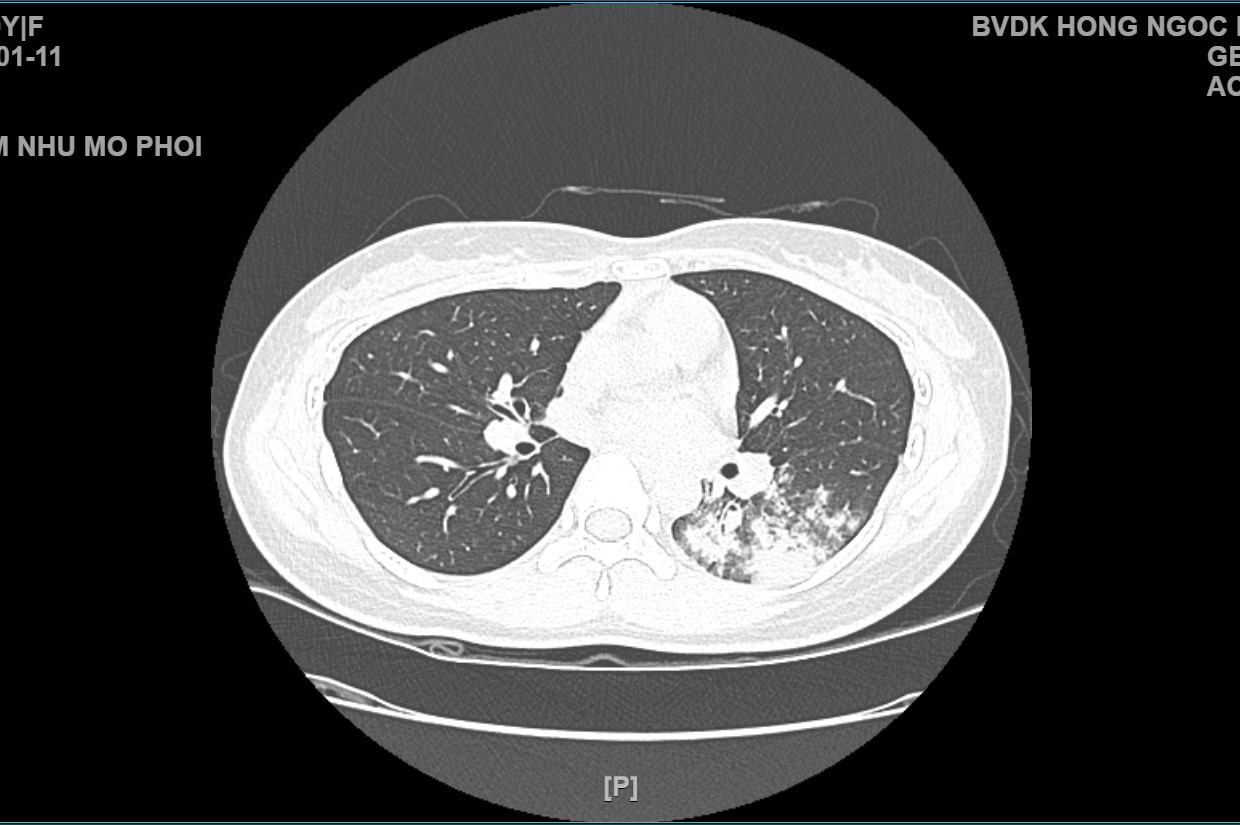

width= Hình ảnh chụp X-quang và phim chụp cắt lớp vi tính ở ngực bệnh nhân